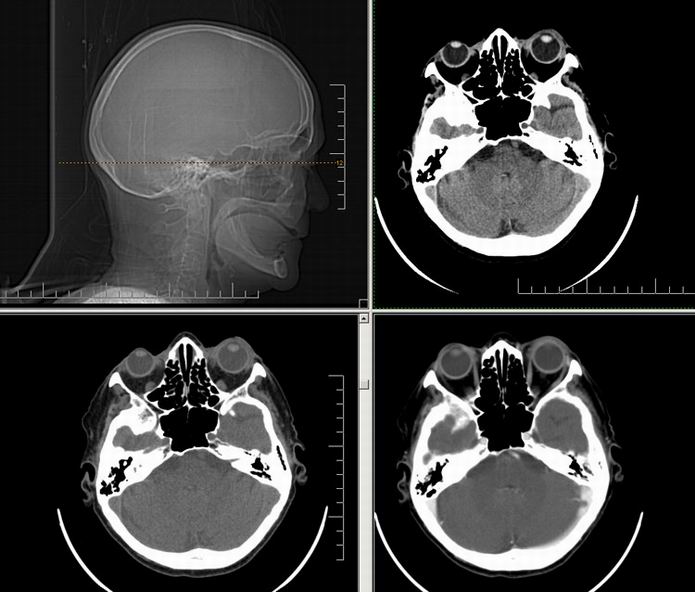

Est ce que qqun a des coupes axiales de crâne pour m'aider à réviser mon anatomie. Merci

Pour compléter tes révisions, Poupette vient de nous faire parvenir ces planches bien utiles: Planches de coupes axiales cérébrales, dans la rubrique COURS / ANATOMIE